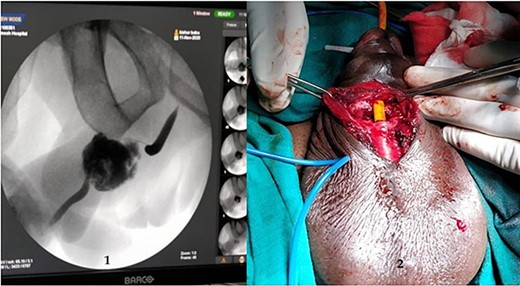

A 37-year-old male presented with a history of a ‘snap’ sound and immediate detumescence of penis during intercourse, when he fell and hit the pubic bone of his partner. There was generalized swelling and pain in the penis. There was acute retention of urine, an attempt to pass a catheter failed and the patient underwent supra-pubic catheterization. On examination, there was classical ‘eggplant deformity’ of the penis with blood at the tip of the meatus. MRI showed a tunical tear on both sides at the penoscrotal junction with indistinct urethra and extensive hematoma in the proximal penile shaft (Fig. 1). With the diagnosis of a fractured penis and possible urethral injury, after proper counselling, the patient was taken up for surgery. On the table, a retrograde urethrogram (RGU) was done showing evidence of partial urethral disruption. On exploration with penoscrotal vertical incision, there was total transection of proximal penile urethra, and a 1.5 cm tunical injury of corpus cavernosum on both sides ventrally (Fig. 2). There was extensive hematoma. Corpora sutured with 4.0 prolene after reconstructing the midline septum. Urethral ends mobilized and anastomosed with 3.0 vicryl in a single layer with minimal spatulation (Fig. 3). The patient was discharged on the 5th post-operative day; Foley catheter was removed on day 21. Follow-up RGU done after 3 months showed no evidence of stricture (Fig. 4).

(1) On table RGU showing evidence of partial urethral disruption and (2) total transection of proximal urethra on exploration with penoscrotal vertical incision.